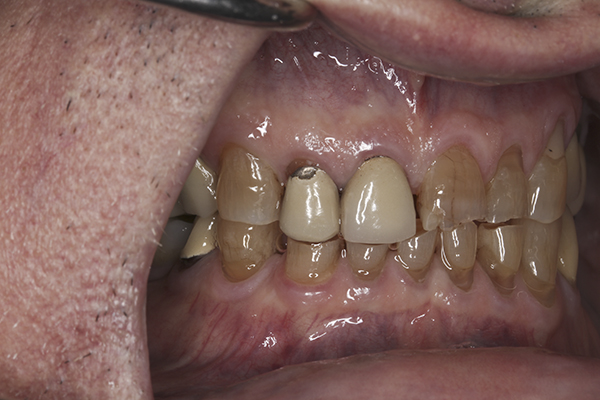

(10.) Preoperative anterior, closed view. Note the end-to-end occlusion of the anterior teeth and the wear on the incisors and centrals resulting in no anterior or canine guidance.

Figure 10